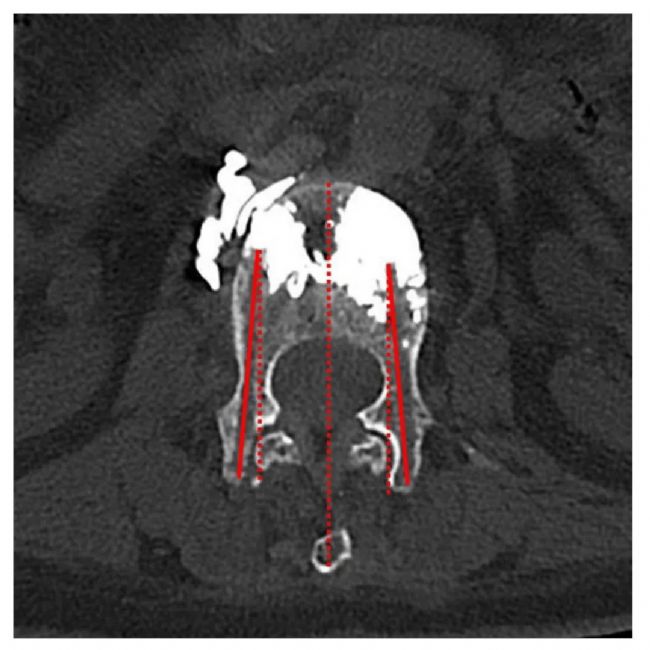

❐ 數(shù)據(jù)收集:收集了OVCF患者的基線特征,包括年齡、性別、BMDT值和椎體骨折部位。從術(shù)前、術(shù)后和術(shù)后3個(gè)月隨訪的腰椎正側(cè)位片上判斷骨水泥的彌散程度。手術(shù)過程中,記錄使用C形臂的透視次數(shù)、總輻射劑量以及是否存在骨水泥滲漏。使用VAS疼痛評(píng)分評(píng)估患者椎體骨折后的疼痛,使用ODI評(píng)分評(píng)估患者的恢復(fù)和康復(fù)情況。記錄了術(shù)前、術(shù)后3天和術(shù)后3個(gè)月的VAS和ODI評(píng)分。根據(jù)術(shù)后隨訪CT掃描中患者病椎的橫截面測(cè)量并記錄了穿針的外展角度。

① 根據(jù)術(shù)后隨訪CT的橫截面測(cè)量穿刺外展角,兩組之間存在顯著性差異(P<0.05)。

④兩組之間骨水泥彌散的程度:使用ImageJ軟件評(píng)估骨水泥的彌散程度,結(jié)果分為四類:I度代表骨水泥在正側(cè)位片上的覆蓋面積均小于50%;Ⅱ度代表骨水泥在正位或側(cè)位片上的覆蓋面積大于50%小于75%;Ⅲ度代表骨水泥在正側(cè)位片上的覆蓋面積均大于50%小于75%;IV代表骨水泥在正側(cè)位片上的覆蓋面積均超過75%,兩組間差異有統(tǒng)計(jì)學(xué)意義。

術(shù)后X線顯示骨水泥的彌散。與PVP組相比,R-PVP組在術(shù)后X線片上表現(xiàn)出更強(qiáng)的在椎體中線的融合能力。